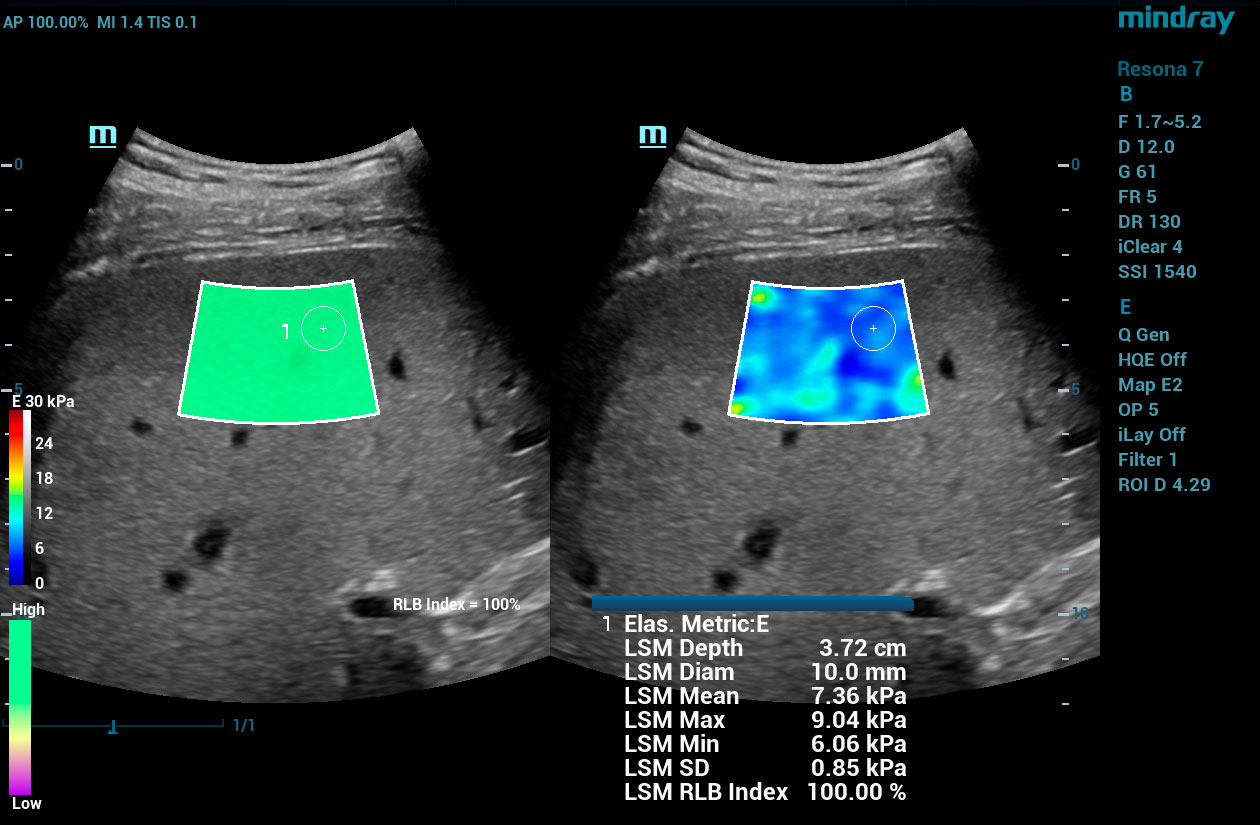

To address the changing needs of today’s value-based care environment, the Resona 7 Ultrasound System Platinum Edition was developed to capture clear, uniform images for radiology, vascular, women’s health, pediatric, and shared service imaging applications.

Premium imaging coupled with advanced workflow technologies help ease clinicians’ increasing workload by offering intuitive and easy-to-use smart tools and AI-enhanced technologies to elevate clinician and patient satisfaction. The user-directed ergonomic design is ideal for daily use, enabling clinicians to capture premium images without sacrificing comfort.